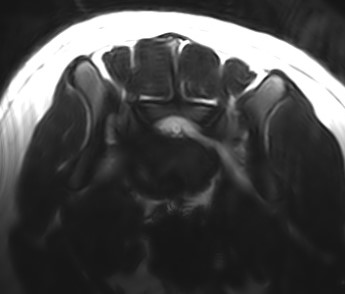

Other diagnostic tests include computed tomography (CT) and magnetic resonance imaging (MRI). Some veterinary practices do not have CT and MRI equipment, so referral to a specialist is a good idea.